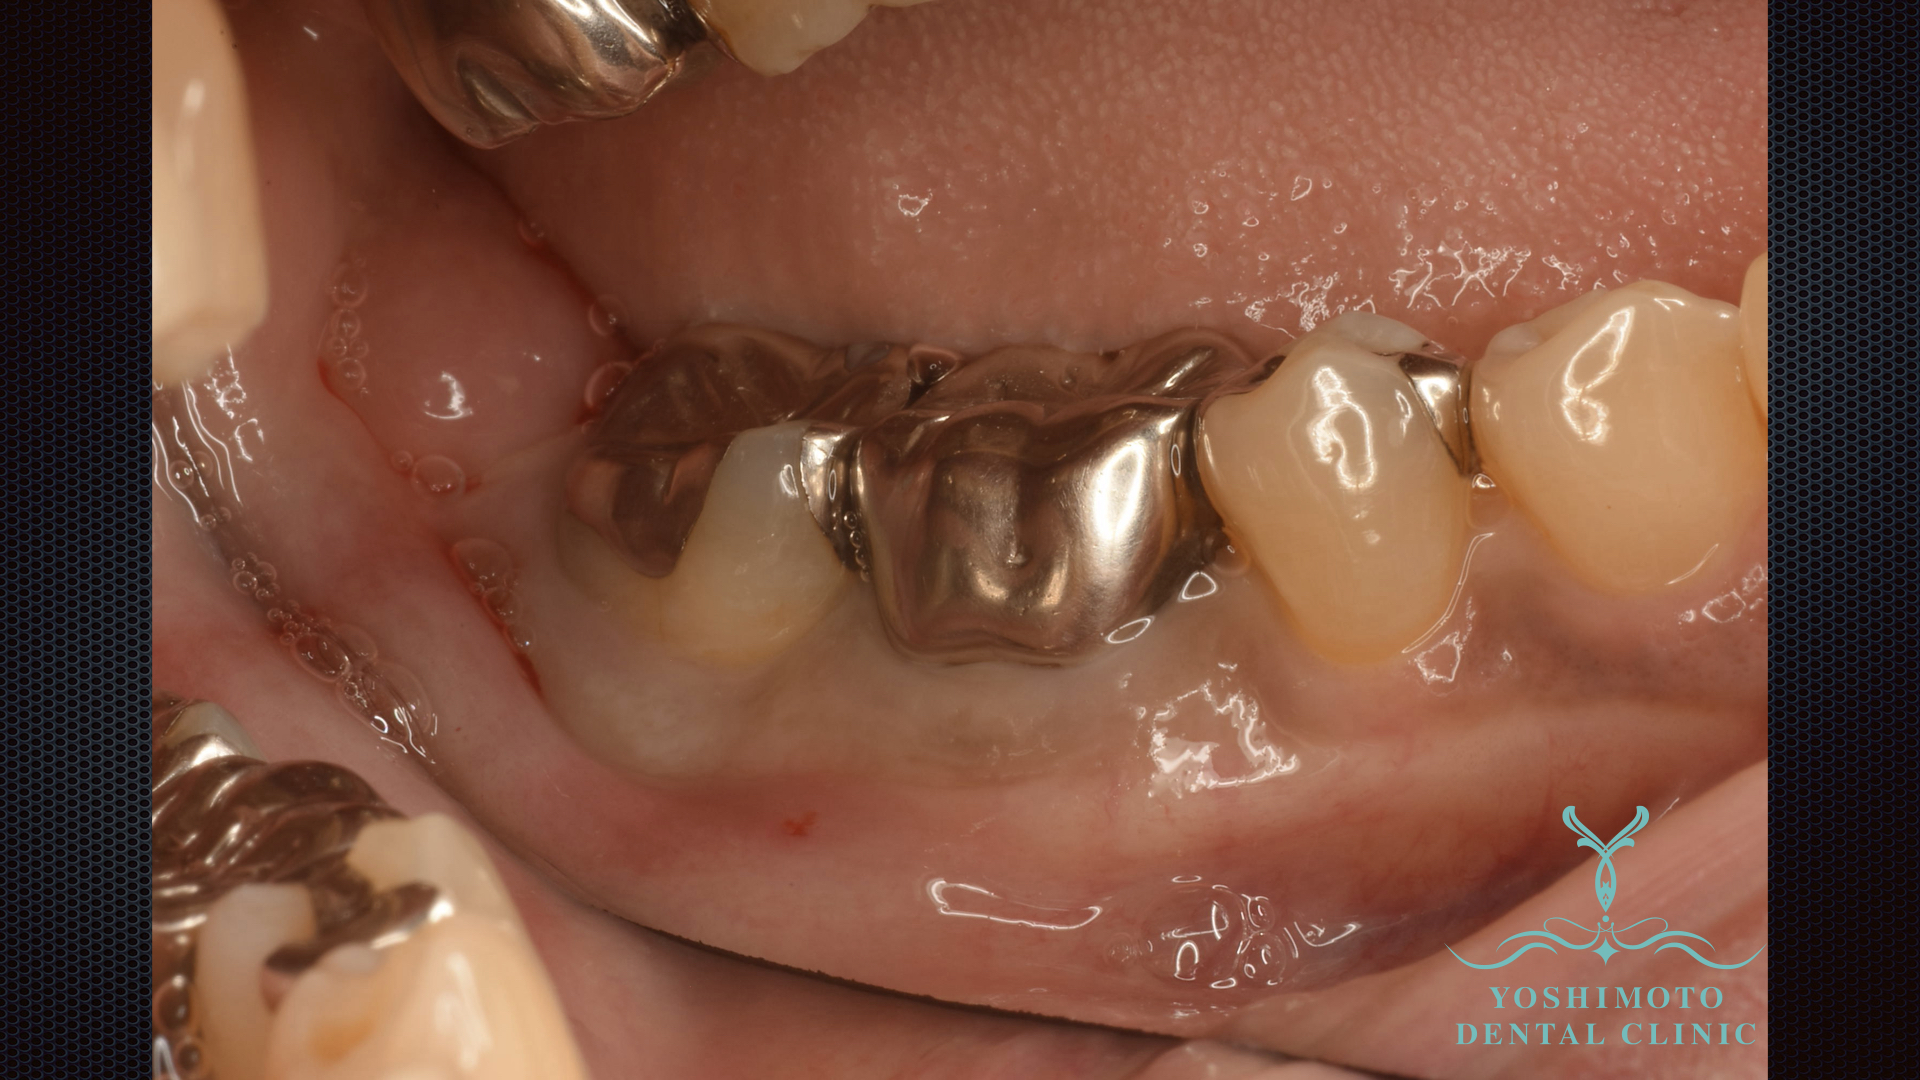

⇧歯周外科手術時の写真です。

レントゲン所見でも最後臼歯に垂直性の骨吸収が確認されました。

局所麻酔下にて切開を行い、歯肉弁を剥離し徹底的にデブライドメントを行い、リグロスによる歯周組織再生療法を試みました。